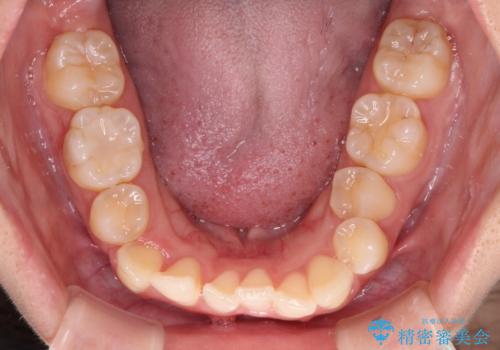

八重歯の抜歯矯正 補助装置とワイヤーを併用したインビザライン矯正治療

インビザラインによる矯正治療を希望されたため、八重歯改善のための抜歯矯正部分や上顎正中の大幅に位置移動は、補助装置やワイヤー矯正を併用し、その後はインビザラインにて行うこととしました。

骨格的に下顎が左側に変位していたため、上下正中を合わせることは困難であることは分かっていましたが、可能な限り合わせることができました。

骨格的なズレがあると仕上げの段階で奥歯の咬み合わせが不安定となるため、予定よりやや長期間となりました。